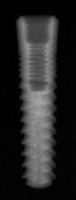

SwishPlant

Connection Interface

Internal interface

Body Shape

Tapered apexTapered body

Thread Design

MicrothreadsThreaded

Additional Features

Curved apexFlared flangeimplantReverse buttress